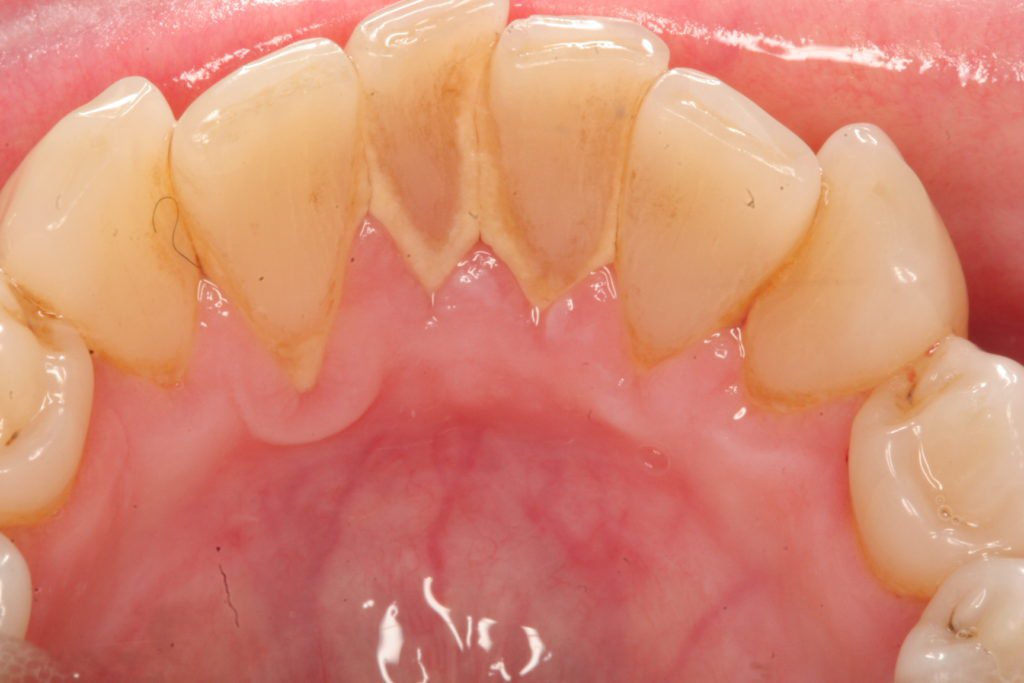

Hình ảnh cao răng của bệnh nhân

Cao răng, hay còn được gọi là vôi răng, là một lớp mảng bám cứng tồn tại trong khoang miệng, hình thành từ sự lắng đọng của các khoáng chất trong nước bọt cùng với các vi khuẩn và phần dư thừa của thực phẩm. Được hình thành cả ở bề mặt trên và dưới đường viền nướu, nếu không được làm sạch kịp thời, cao răng có thể trở thành

mối đe dọa cho sức khỏe răng miệng của bạn.

Mỗi ngày, trong khoang miệng của chúng ta chứa hàng triệu vi khuẩn; khi không vệ sinh răng miệng đúng cách sau khi ăn, các vi khuẩn này sẽ kết hợp với mảnh vụn thức ăn tạo nên mảng bám – một chất dẻo mềm. Qua thời gian, nếu không được làm sạch định kỳ, mảng bám này sẽ cứng lại và chuyển hóa thành cao răng, mà việc chỉ chải răng đơn thuần không thể loại bỏ.